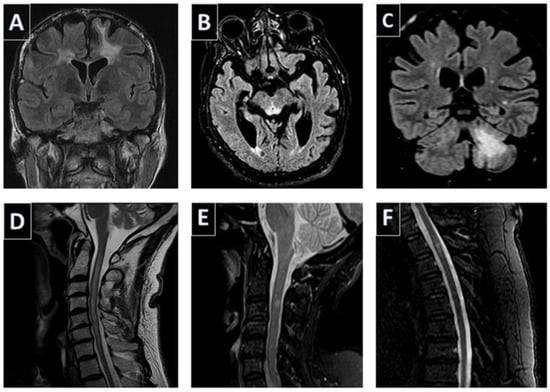

- Boziki, M.; Metallidis, S.; Habidou, E.; Afrantou, T.; Bakirtzis, C.; Cheva, A.; Finitsis, S.; Grigoriadis, N. Progressive multifocal leukoencephalopathy in an elderly immunocompetent-appearing patient: Relevance with L-selectin (CD62L) expression and immunosenescence. Clin. Neurol. Neurosurg. 2021, 205, 106625. [Google Scholar] [CrossRef]